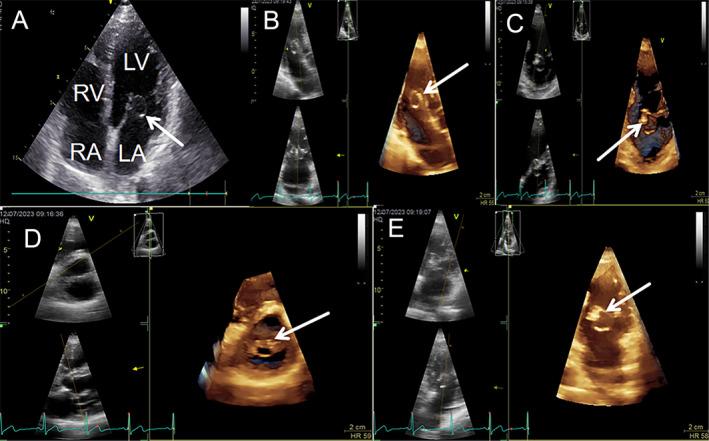

两名成年人中偶然发现孤立的副二尖瓣组织

Incidental Finding of Isolated Accessory Mitral Valve Tissue in Two Adults.

Accessory mitral valve tissue is a rare congenital anomaly often linked to the anterior mitral leaflet, diagnosed via echocardiography. It may cause left ventricular outflow tract obstruction, with prognosis depending on obstruction severity and regular monitoring essential in asymptomatic cases.

二尖瓣附属组织是一种罕见的先天性异常,常与二尖瓣前叶相连,通过超声心动图诊断。它可能导致左心室流出道梗阻,预后取决于梗阻的严重程度,对于无症状病例,定期监测至关重要。